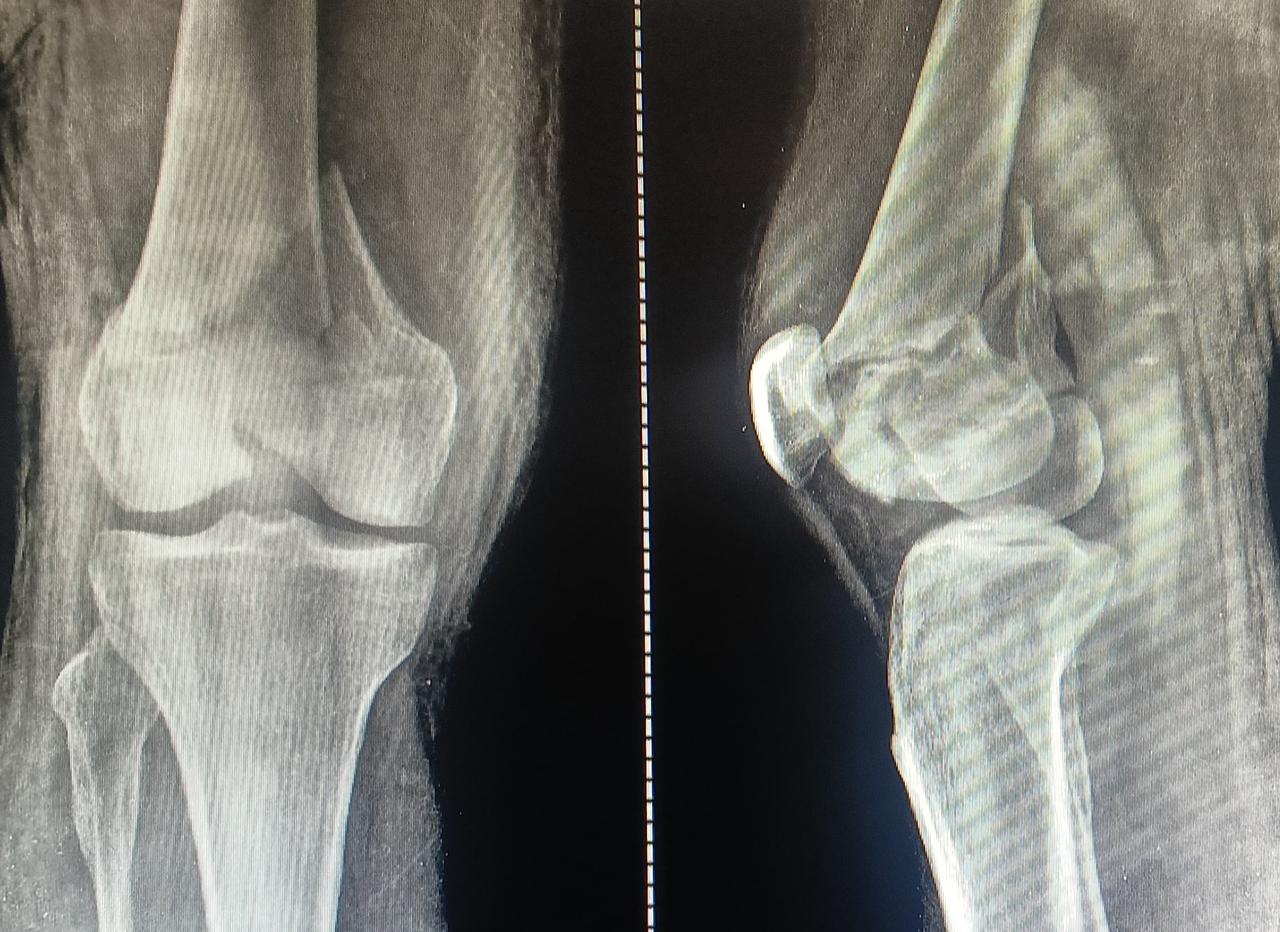

This 48 Year old patient came to us as one such challenging case of femur fracture as shown in xray. Patient also had other injuries which were managed by team of surgeon and doctors at Varunam SuperSpeciality Hospital, Nagpur. As you can see patient had distal femur fracture with joint involvement with severe shattered bone and damage to Articular cartilage. Dr Utsav Agrawal is one of the best orthopaedic surgeon to manage such injuries.